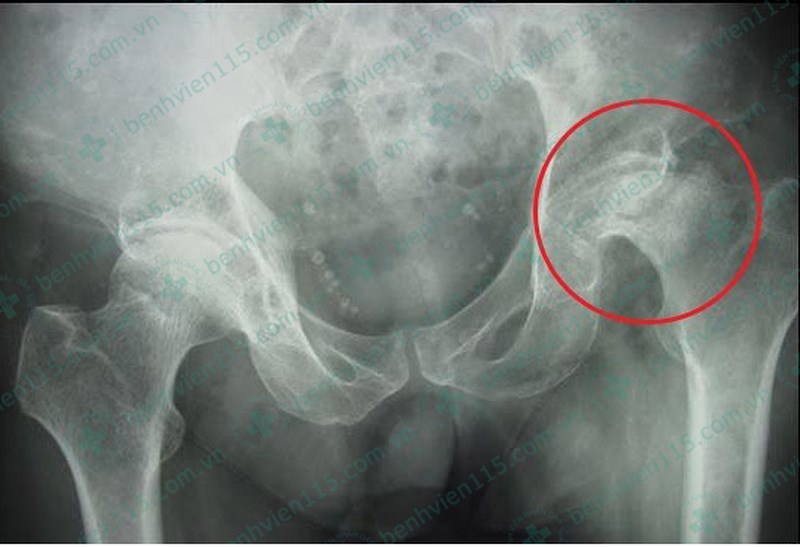

Mới đây, BV Nhân dân 115 thành phố Hồ Chí Minh tiếp nhận ông V.V.T. (46 tuổi, ở TP HCM) trong tình trạng đau khớp gối cùng bên khớp háng phải.

Sau khi chẩn đoán, các bác sĩ (BS) kết luận ông T. bị hoại tử chỏm xương đùi, nguyên nhân chính dẫn đến tình trạng này là do rượu bia và thuốc lá. Bản thân ông T. cũng cho biết đã "làm bạn" với rượu bia, thuốc lá từ năm 20 tuổi.

Để ông T. có thể đi đứng bình thường, các BS buộc phải phẫu thuật khớp háng. Đồng thời yêu cầu ông ngưng ngay rượu bia, thuốc lá.

ThS-BS Ngô Thị Cẩm Hoa, phụ trách khoa Khám và điều trị theo yêu cầu, BV Nhân dân 115, cho biết nguyên nhân chủ yếu gây hoại tử chỏm xương đùi ở nam giới là do lạm dụng rượu bia và thuốc lá.

Kết quả chụp X-quang cho thấy bệnh nhân bị hoại tử chỏm xương đùi. |

“Chỏm xương đùi là một bộ phận tạo thành khớp háng. Rượu bia, thuốc lá là yếu tố chính làm tổn thương viêm mạn tính và làm tắc các mao mạch nuôi chỏm xương đùi, làm chỏm xương đùi bị hoại tử do thiếu máu nuôi" - BS Hoa nói.

Cũng theo BS Hoa, vùng hoại tử lúc đầu chỉ là vùng thưa xương và các ổ khuyết xương. Dần dần dẫn đến tình trạng gãy xương dưới sụn và giai đoạn cuối là gây xẹp chỏm xương đùi. Hiện tượng trên làm mất chức năng bình thường của khớp háng khiến người bệnh trở nên tàn phế.

Hoại tử chỏm xương đùi diễn biến âm thầm, từ từ cho đến khi người bệnh bắt đầu cảm nhận được cảm giác đau ở khớp háng bị tổn thương. Ở giai đoạn này đồng nghĩa bệnh đã tiến triển đến giai đoạn trung bình trở lên. Một số trường hợp không có triệu chứng đầu tiên đau tại khớp háng mà trong giai đoạn sớm người bệnh có cảm giác đau khớp gối cùng bên khớp háng bị tổn thương. Chính vì vậy, một số bệnh nhân dễ bị chẩn đoán là thoái hóa khớp gối hay bệnh lý tại khớp gối thay vì chẩn đoán hoại tử chỏm xương đùi giai đoạn sớm.

Theo BS Hoa, khoảng 80% nam giới trong độ tuổi từ 40 đến 50 bị hoại tử chỏm xương đùi. Tuy nhiên, hiện nay bệnh đang có xu hướng trẻ hóa, đáng lo ngại là nhóm nam thanh niên trong độ tuổi 30 đã có biểu hiện căn bệnh nói trên do thường xuyên sử dụng rượu bia và thuốc lá.

“Những người nằm trong nhóm nguy cơ cao nêu trên và kèm theo biểu hiện đau khớp háng một bên hay hai bên khi ngồi xổm thì hãy nghĩ ngay tới hoại tử chỏm xương đùi. Chưa hết, đau khi đi nhiều hoặc đứng lâu hoặc có biểu hiện đau khớp gối dai dẳng mà chưa tìm ra nguyên nhân tổn thương tại khớp gối thì nên tới các BV có chuyên khoa cơ xương khớp để được chẩn đoán sớm và điều trị kịp thời” - BS Hoa khuyến cáo.